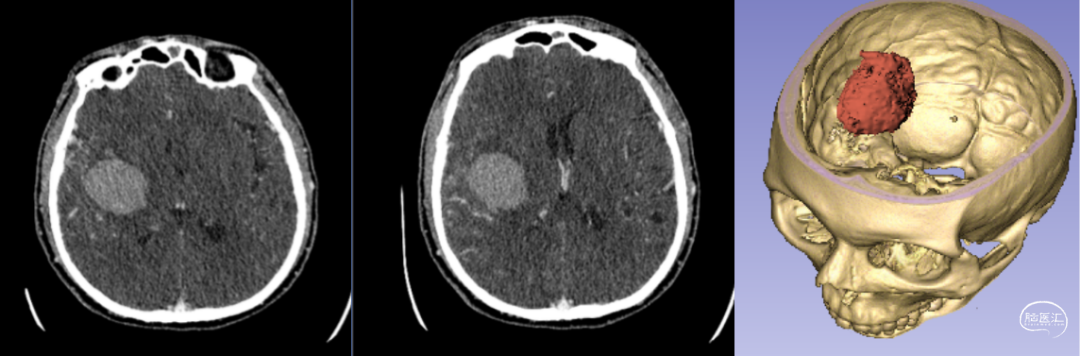

7.1 3D打印技術(shù)定位下腦內(nèi)血腫穿刺術(shù)

3D打印可以制作個(gè)性化的手術(shù)導(dǎo)板。在神經(jīng)外科手術(shù)中,手術(shù)導(dǎo)板可以幫助醫(yī)生更準(zhǔn)確地進(jìn)行鉆孔、切割等操作。在顱骨鉆孔時(shí),定制的3D打印手術(shù)導(dǎo)板能夠確保鉆頭準(zhǔn)確地到達(dá)病變部位,提高手術(shù)的精準(zhǔn)性。

新疆醫(yī)科大學(xué)第一附屬醫(yī)院神經(jīng)外科中心已成功將該技術(shù)應(yīng)用于多例腦卒中患者的治療。以一例典型病例為例:[14]

- 患者情況:52歲女性,因“右側(cè)肢體無力1天”就診,入院時(shí)呈淺昏迷狀態(tài),雙側(cè)瞳孔等大等圓(直徑約3.5mm),對(duì)光反射遲鈍,右側(cè)肢體肌力為0級(jí)。

- 手術(shù)過程:基于術(shù)前影像數(shù)據(jù),團(tuán)隊(duì)利用3D打印技術(shù)設(shè)計(jì)并制作個(gè)性化手術(shù)導(dǎo)板,精準(zhǔn)定位血腫位置后實(shí)施穿刺引流。術(shù)后復(fù)查頭部CT顯示,引流管準(zhǔn)確位于血腫腔內(nèi),血腫清除效果良好。